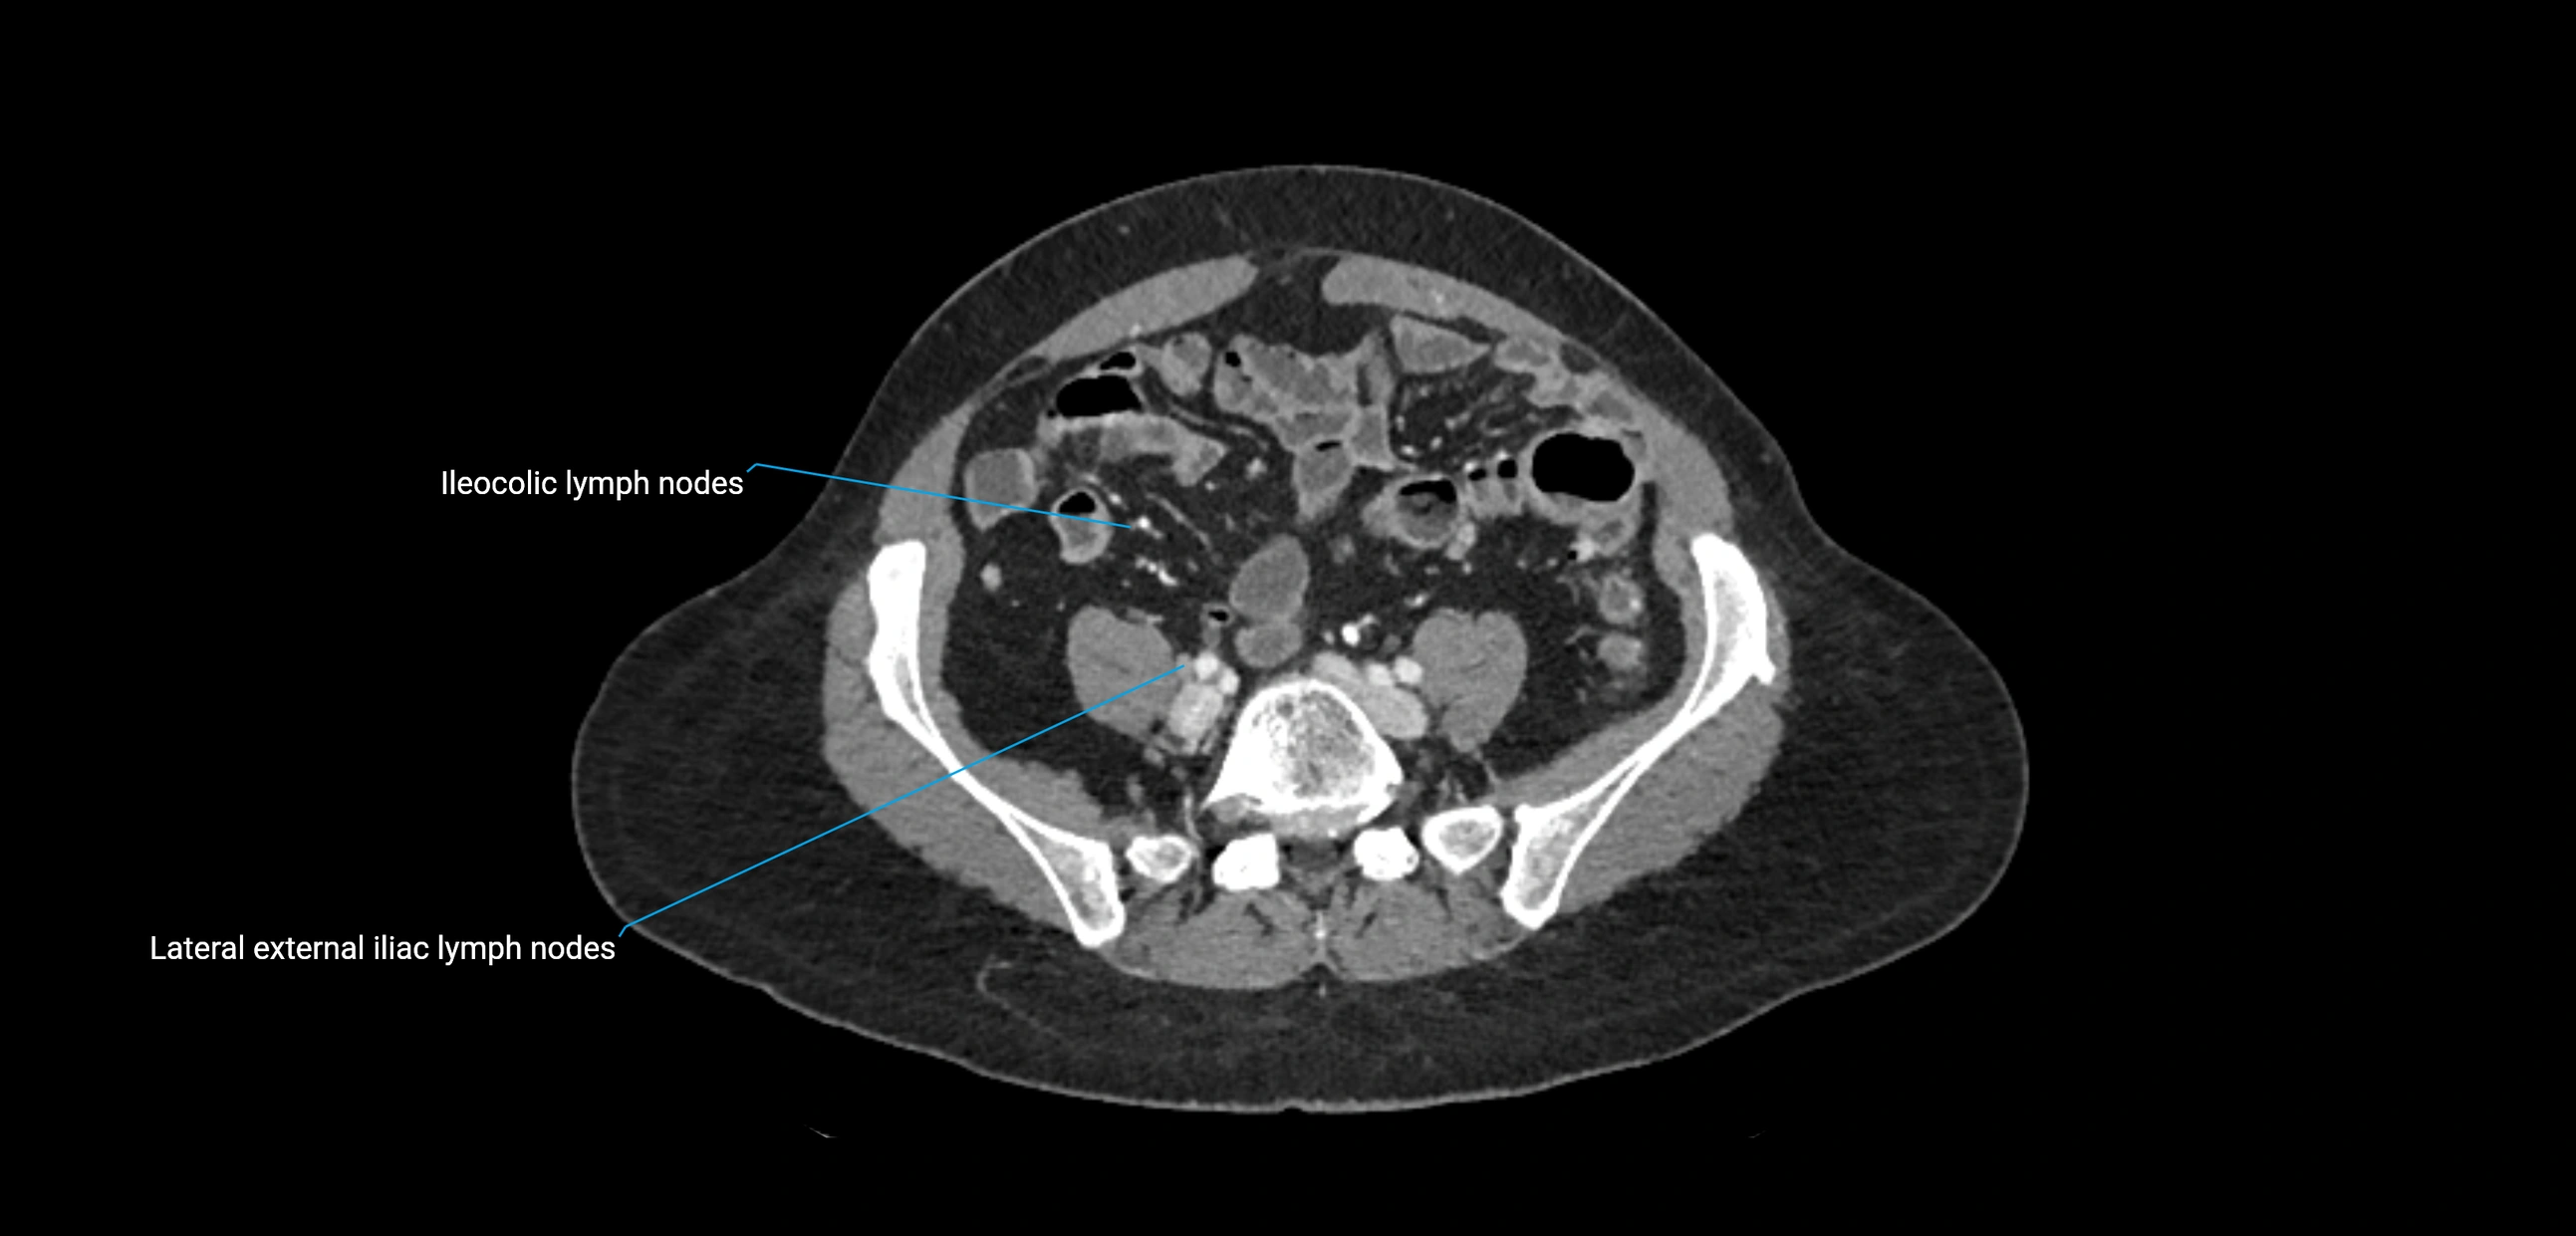

CT image

image